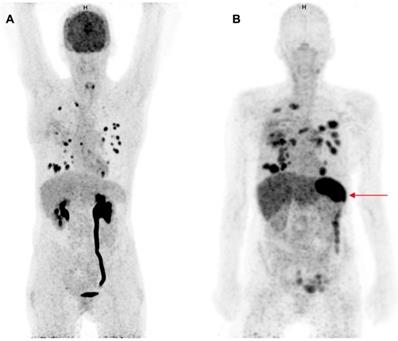

Two clinical studies have been published in which therapeutic anti-PD1 or anti-PD-L1 mAbs have been radiolabeled for PET imaging of the PD-1:PD-L1 checkpoint. This approach can provide information about their tumor penetration and target engagement. One trial was performed with 10 mg of the PD-L1 antibody atezolizumab radiolabeled with zirconium-89 (89Zr) and PET imaging on days 4 and 7 in patients with NSCLC, cancer of the urinary tract, and triple negative breast cancer prior to atezolizumab treatment (figure 1) (49). 89Zr-atezolizumab tumor uptake was positively associated with a response rate to atezolizumab treatment. Moreover, the geometric mean uptake of 89Zr-atezolizumab above or below median correlated to progression free survival (PFS) and OS. For individual lesions, higher 89Zr-atezolizumab tracer uptake is associated with tumor size reduction over time. In contrast, PD-L1 expression in tumor biopsies, obtained 7 days after tracer injection and immediately after the last PET scan, did not correlate with response to therapy. Tracer uptake was also seen in lymphoid tissues such as normal lymph nodes, tonsils and the spleen. Since PD-1:PD-L1 inhibitors induce a systemic immune response with effects throughout the body, tracer uptake measured with PET in normal tissues might also serve as a proxy for evaluation of activation of the immune system. Uptake of the tracer was also seen in sites of inflammation, including a sinusitis and a knee bursitis. Another study reported high 89Zr-atezolizumab uptake in a mouse bearing a tumor graft model of a patient with metastatic clear cell renal cell carcinoma. This patient later appeared to have a durable response to nivolumab treatment (50).

Comparison of 18F-FDG-PET and 89Zr-atezolizumab-PET imaging. Maximum intensity projections of 18F-FDG-PET, 1 h after tracer injection (A) and 89Zr-atezolizumab-PET, 7 days after tracer injection (B) of a 53 year old woman diagnosed with NSCLC. Both imaging modalities show uptake in multiple intra-pulmonary metastases. The 18F-FDG-PET scan shows physiological high uptake in the brain and excretion via the kidneys. At the moment of this scan the patient had a post-renal obstruction due to a kidney stone. The 89Zr-atezolizumab-PET scan shows high uptake in the spleen (red arrow). The 18F-FDG-PET scan was performed 46 days prior to the 89Zr-atezolizumab-PET scan. Both scans were scaled equally (0-8).